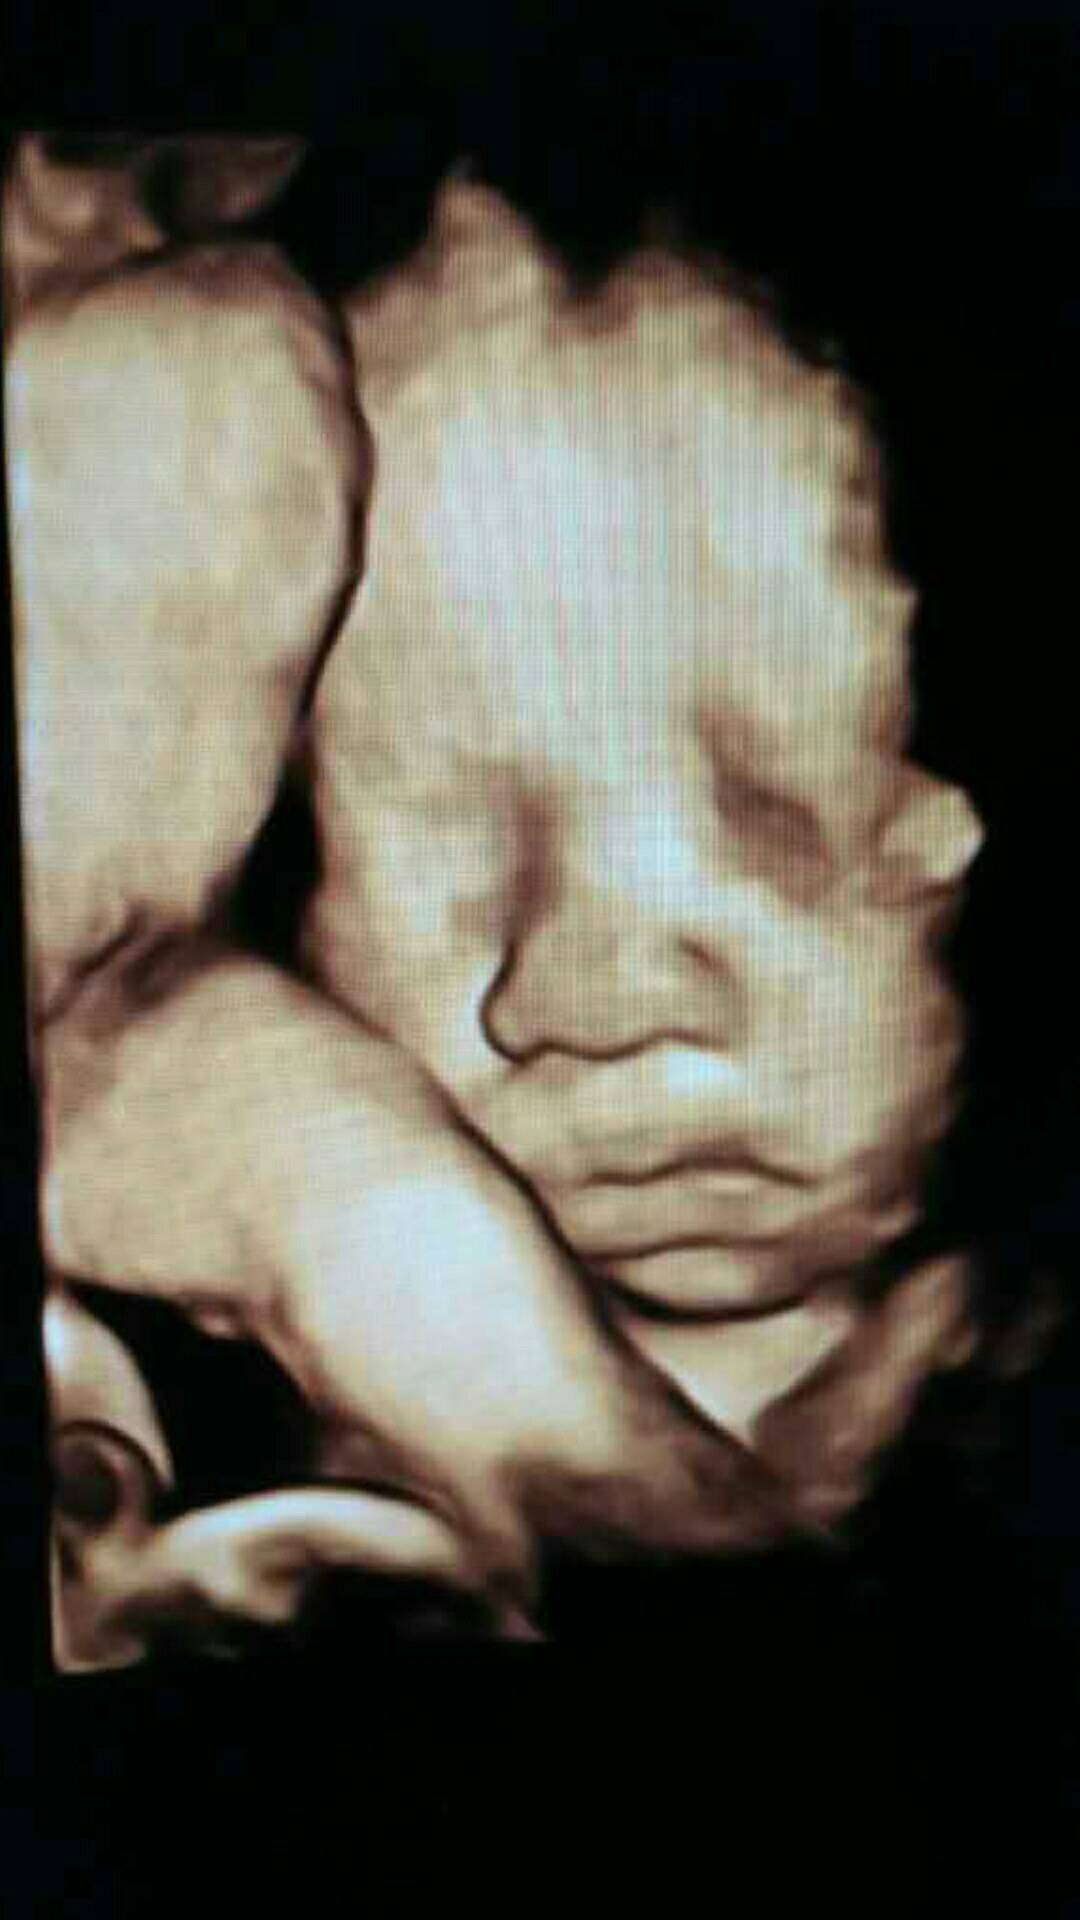

孕后期身上出现出血点,孕37周确诊红斑狼疮,38周剖腹产生出一个可爱的儿子。